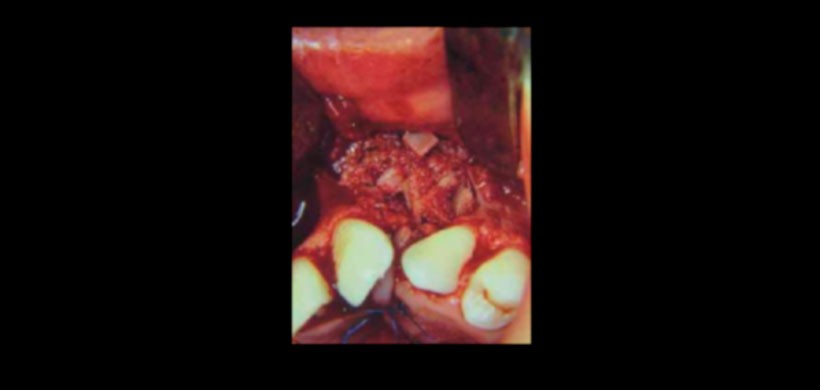

Figura 3: Una cantidad suficiente de tejido óseo a injertar en la fi sura nasoalveolar es una de las características que aporta esta técnica, optimizando así los objetivos que persigue el injerto nasoalveolar.

Figura 2: La técnica descrita por el Dr. Phillipe J. Boyne permite una adecuada visualización de la fi sura nasoalveolar, lo que favorece un adecuado cierre del piso nasal.